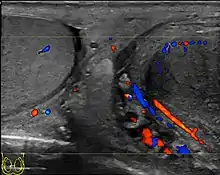

At ultrasound, tuberculous epididymitis is characterized by an enlarged epididymis with variable echogenicity. The presence of calcification, caseation necrosis, granulomas and fibrosis can result in heterogeneous echogenicity [Fig. 21a]. The ultrasound findings of tuberculous orchitis are as follow: (a) diffusely enlarged heterogeneously hypoechoic testis (b) diffusely enlarged homogeneously hypoechoic testis (c) nodular enlarged heterogeneously hypoechoic testis and (d) presence of multiple small hypoechoic nodules in an enlarged testis [Fig. 21b].

Although both bacterial and tuberculous infections may involve both the epididymis and the testes, an enlarged epididymis with heterogeneously hypoechoic pattern favors a diagnosis of tuberculosis (Muttarak and Peh, 2006, as cited in Kim et al., 1993 and Chung et al., 1997). With color Doppler ultrasound, a diffuse increased blood flow pattern is seen in bacterial epididymitis, whereas focal linear or spotty blood flow signals are seen in the peripheral zone of the affected epididymis in patients with tuberculosis.